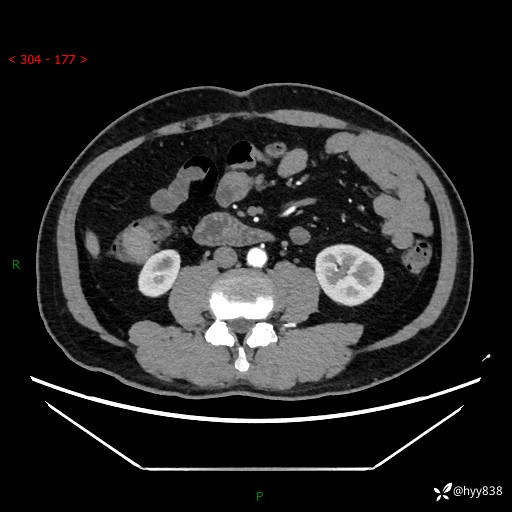

腹部CT增强扫描(外院CT平扫)

两期CT值:75hu 82hu